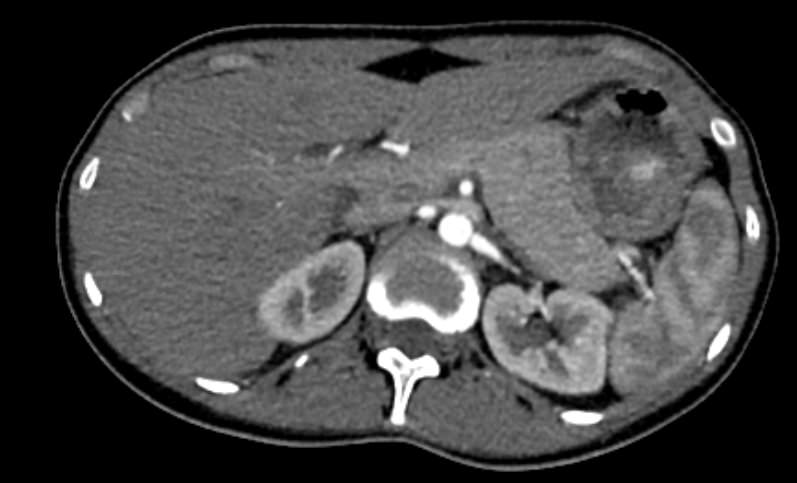

Мультиспиральная КТ сосудов почек (КТ-ангиография) с внутривенным болюсным контрастированием проводится для диагностики патологии почечных артерий. С помощью КТ-ангиографии можно выявить врожденные аномалии развития сосудов почек, диагностировать стенозы (уменьшение просвета) почечных артерий за счет развития атеросклеротических бляшек.

КТ сосудов почек применяется для выявления признаков вторичной артериальной гипертензии, при планировании оперативных вмешательств и для оценки успешности проведенной операции на сосудах. КТ ангиография почечных артерий позволяет оценить их анатомию, выявить добавочные и аберрантные почечные сосуды, определить типично ли они распространяются в ворота почки или заходят в паренхиму через корковый слой.

Чувствительные детекторы улавливают рентгеновские лучи после их прохождения сквозь тело человека. На основании этих данных получаются изображения сосудистой системы почек в мельчайших подробностях. Кроме того, с помощью цифровой обработки данных томограф реконструирует трехмерные модели кровеносных сосудов на уровне исследуемой области. 3D-реконструкции помогают увидеть пространственное соотношение анатомических структур и значительно повышают качество диагностики.

Ангиография почечных артерий может показать наличие:

• сужения кровеносных сосудов почек (почечный стеноз);

• доброкачественных или злокачественных опухолей;

• острую артериальную окклюзию почки (инфаркт почки);